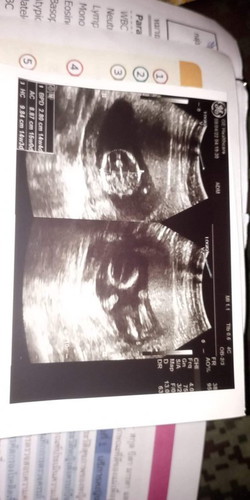

ท้องที่2ตอนนี้14w5d ยังไม่ทราบเพศ ลูกสาวคนเเรก8ปีกว่าเเล้ว เเม่ภาวนาให้เป็นชายน่ะ รักมากคนเเปรกหน้าที่อยากเจอ